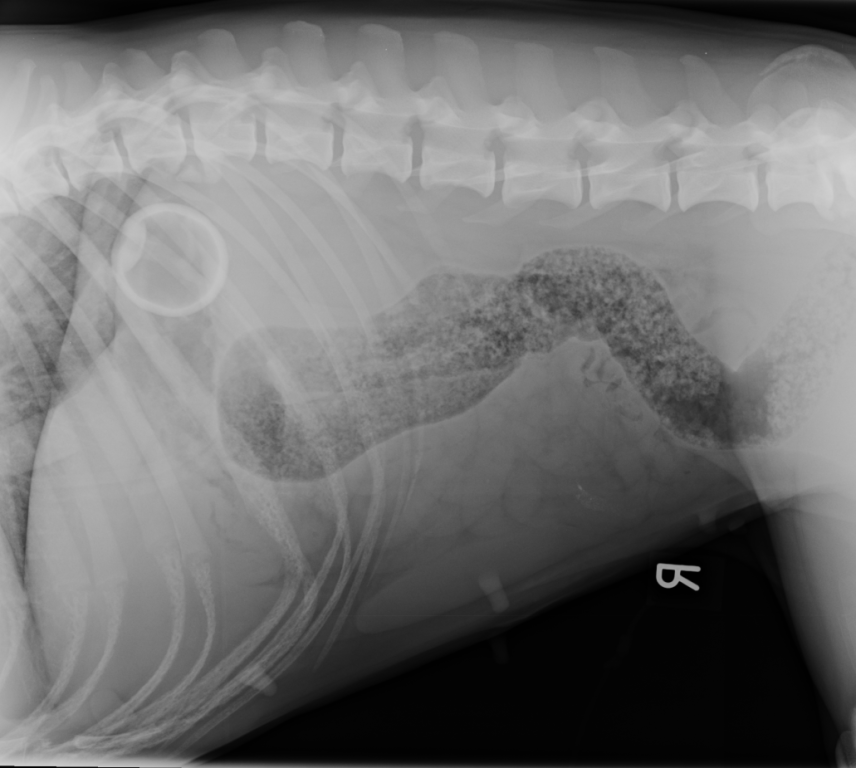

Dr May said: “I was very concerned about the potential consequences when a chest x-ray revealed the ball was in the stomach.

“An X-ray confirmed the location of the ball was still present within Bonnie’s stomach. I was concerned the ball may cause inflammation of the stomach lining (gastritis) or an obstruction in her intestine. So, in order to avoid an operation to remove the ball, Bonnie underwent endoscopy under an anaesthetic.”